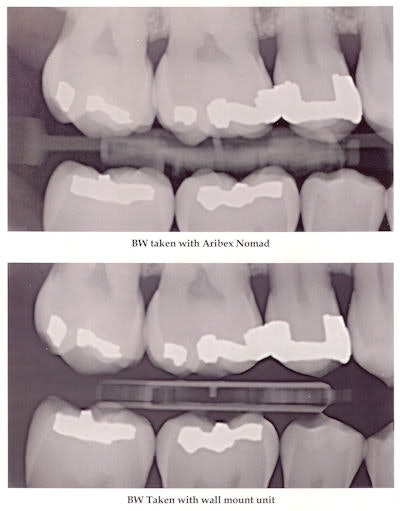

With regard to image quality, Turner said that blurring isn't possible with the short exposure time: 0.2-0.3 seconds. Also, the Nomad uses the smallest focal spot available (0.4 mm), which Turner said further improves the image quality.

Dr. Danforth noted that the image quality can vary depending on what type of film is used. The UNLV dosimetry studies involving digital sensors and F-speed film resulted in image quality "well within [the] acceptable range and not blurred, as some uninformed individuals want to imply," he told DrBicuspid.com. Ultra D-speed film, however, requires a longer exposure and could be subject to some motion artifact, he added.

"In general, I have favorable views concerning the newer version of the Aribex Nomad for use in making a limited number of exposures, such as bitewings and occasional periapicals," Allan Farman, B.D.S., M.B.A., Ph.D., D.Sc., a professor of radiology at the University of Louisville of Kentucky, stated in an e-mail to DrBicuspid.com. "I was not so impressed by the older version, as the battery was quite heavy and use could tire the operator, which in turn could lead to motion unsharpness. The newer version uses much lighter batteries and is a vast improvement."